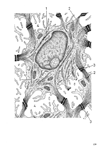

表皮【ひょうひ】 Outer layer of skin covering the body, ranging in thickness from 30 Jim to 4 mm or more. It is stratified and keratinized, and consists of squamous epithelial cells.(表皮は皮膚の最表層を占める重層扁平上皮で、その最表層は上皮細胞が死滅し、乾燥した鱗片となり、角質層とよばれる。角質はケラチン(keratin)という硬蛋白の線維状のミセルが密に集合してできており、角質を形成する現象を角化と呼ぶ。手掌、足底の表皮は非常に厚い角質層を有し、その底部はエオジンに好染する明るい層として、淡明層とよばれるが、角質層の一部と考えてよい。角質層の細胞は死滅して、核を失っているが、その下方にある数層の上皮細胞は核を有し、種々の代謝活動を有している。表皮の深部にある、そのような生きている細胞の層を一括してマルピギー層(Stratum malpighii)ということがある。表皮を真皮から剥離して下面をみると、真皮乳頭に対応する所が凹みとなり、その凹みの間がもり上がった網状にみえるので、これをマルピギー網(Rete malpighii)とよんだのがはじまりである。マルピギー層は3層に分けられ、角質層に接する顆粒層、中間部のやや厚い数層の細胞から成る有棘層、最深部で真皮に接触する基底層(円柱層ともよぶ)に区分する。基底層は通常1層のやや高い円柱あるいは立方形の細胞からなっており、ここで細胞が分裂して増殖するので、胚芽層ともよばれる。胚芽層という語はマルピギー層と同義語に用いられることがありその場合は有棘層、顆粒層をも含む。表皮細胞(epidermocyte)は基底層で分裂新生し、次第に表層に移行して、最後には角化死滅して、剥離する。この期間は通常15~30日といわれる。このように必ず角化する細胞であるから、角化細胞(keratinocyte)ともよばれる。この細胞は互いにデスモゾームによって連結し、細胞内には多量の張細糸(tonofilaments)が含まれ、細胞周辺にあるデスモゾームに集中付着している。張細糸はしばしば集まって束をつくり、張細線維(tonofibrilis)とよばれる。張細線維は光顕でみえるが、張細糸は電顕でなければ認められない。有棘層の細胞は多数の突起をもった多角形の細胞で、突起の尖端は隣接する同種の細胞とデスモゾームを形成して連結する。このように棘状の突起を有するので有棘細胞(spinous cell)とよばれるのである。有棘層の顆粒がふくまれている。一つはケラトヒアリン顆粒とよぶのである。電顕的には球状のケラトヒアリン顆粒もあるが、大部分は不規則な星状を呈している。表面に膜はなく、その物質は張細糸の間にしみこんで細糸間物質(interfilamentous substance)を形成する。第2の顆粒は板層顆粒(lamellar granules)で、Odland小体、MCG(membrane-coating granule)、ケラチノゾームなどとよばれる。この顆粒は、こまかい平行層板を内部にもっていて、膜によって包まれている。光顕では認められなかったが、電顕でよく観察できる。顆粒はしばしば細胞の表面に開いて、その内容を放出する。この顆粒の機能は不明なところが多く、ある人々は表皮細胞を互いに分離するに役立つ蛋白分解酵素を含み、一種の水解小体であるというが、他の人々は表皮細胞を互いに結合する役目があるという。基底層の表皮細胞は真皮との間を基底膜あるいは基底板(basal lamina)によって境され、細胞表面には基底膜に対する結合装置として、半デスモゾーム(hemidesmosome)を有する。半デスモゾームのない基底表面には微細飲小胞(micropynocytotic vesicle)がみられる。基底細胞に含まれる色素顆粒(メラニン細胞(melanocyte)によってつくられ、一種の食作用によって、表皮細胞がとりこんだものである。表皮に常在する非上皮性細胞は多数の突起を出すゆえに樹状細胞(dendritic cell)とよばれる。その一つはメラニン細胞であって、基底層にあり、多数の突起を上方に出している。この細胞でつくられたメラニン小体(melanosome)またはメラニン顆粒、突起の中に入り、表皮細胞が突起の尖端を貪食することによってメラニンをとりこむ。メラニン細胞内にある未熟なメラニン顆粒をメラニン前小体(premelanosome)といい、これは表皮細胞はLangerhans細胞とよばれ、大食細胞の一種と考えられている。有棘層の上部にあり、特有の板状あるいはラケット状の顆粒(Birbeck顆粒)を含んでいる。)